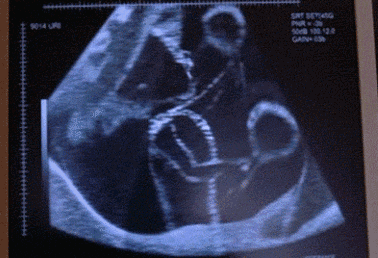

常德丽人妇产医院独家引进韩国麦迪逊

韩国麦迪逊四维彩超是四维彩超技术的发明者,与普通四维彩超相比,在图像质量、探头技术等上实现突破,提供更多、更精准的图像数据,进一步助力精准诊断及早期疾病检查,传递全方位的母婴关爱。

1、测定胎儿年龄

2、分析胎儿的发育情况

3、评价多胞胎和高危妊娠

4、检测胎儿异常